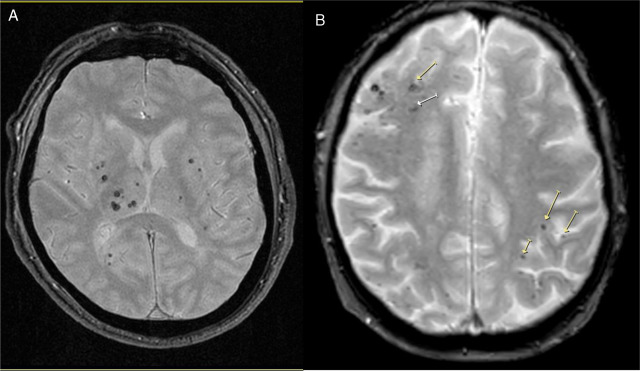

Enfermedad de los vasos cerebrales pequeños en la mediana edad y función cognitiva en etapas posteriores de la vida

20 enero 2025